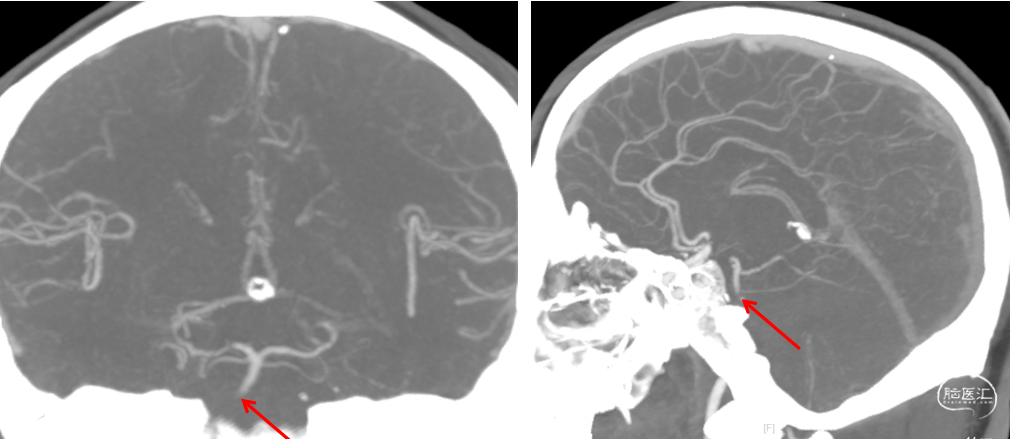

头颈部CTA:右侧椎动脉纤细,双侧椎动脉末端、基底动脉起始段消失,考虑闭塞,请结合临床。

入院头颅CTA(2022-2-2)

1、患者入院时症状较轻,头颈部CTA示:双侧椎动脉V4段及基底动脉中下段未显影,基底动脉上段、双侧大脑后动脉及小脑上动脉显影,考虑基底动脉存在原位狭窄或慢性闭塞,入院后患者病情进展,症状加重,积极行介入治疗。